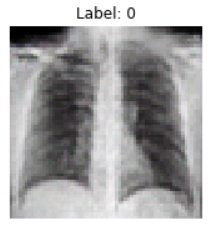

With an x-ray image of an individual's healthy lungs, we are able to use machine learning techniques to add features indicative of COVID-19. Given that we're handling an image, we took an approach that applied the use of Generative Adversarial Networks (GANs) to create a new image of the same lungs except with added COVID-19 properties. COVID-19 may manifest in an x-ray as cloudy regions in the lungs, known as ground glass opacities.

We built an Auxiliary-Classifier GAN (arXiv:1610.09585) that produces lung x-rays with or without COVID-19 properties based on an inputted condition. After the generator has been trained, an inputted healthy lung x-ray is encoded into a latent vector via gradient descent with a VGG perceptual loss (arXiv:1802.05701, arXiv:1603.08155). Then, a condition vector is concatenated with this latent vector and run through the generator to produce the same lung x-ray but with COVID-19 ground glass opacities. This model was written in Pytorch. Hyperparameters and code can be found at the following GitHub. The training data included around 2000 total 64x64 COVID positive and negative x-rays.